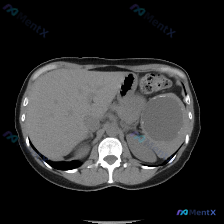

这是一张上腹部CT横断面软组织窗:

- 肝脏:实质密度基本正常,未见明确弥漫性病变或实性占位。

- 脾脏:形态明显失常,内部可见一个巨大的类圆形囊性占位,占据了脾脏大部分体积。

- 关键细节:病变内部是很均匀的低密度,接近水样密度;特别要注意的是,在囊肿的边缘有斑点状、弧线状的高密度钙化影。

- 周围情况:边界相对清晰,周围脂肪间隙还行,没有明显的浸润模糊,但占位效应很明显。